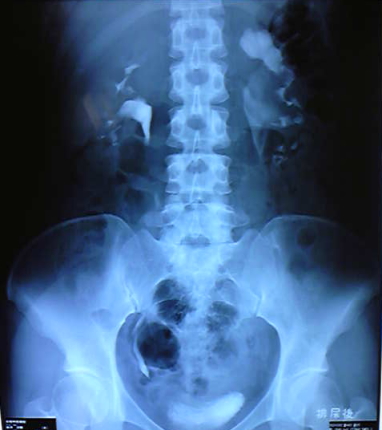

数年前に腎盂尿管移行狭窄症で尿管手術したのですが。。ココ最近調子が悪いです。。

手術したのは左側画像では右側に見えます。

尿管が再狭窄?プラス半水腎症…尿が溜まると左腎臓痛いんです。・゚゚・(>_<)・゚゚・。

今の所カテーテルを入れるとか色々対策を考えてくれてますが多分何も出来なくて我慢でしょう。。